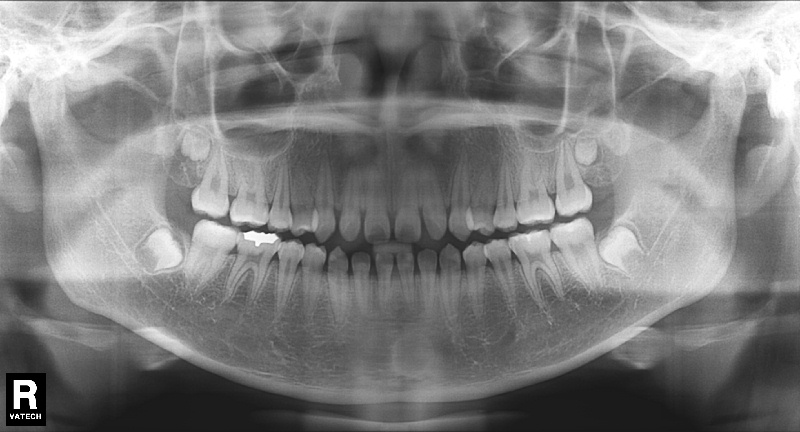

치료 전 사진입니다.